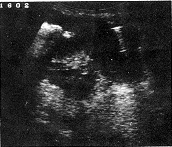

按照小肠肿瘤的超声图像分型〔7〕,本组21例转移性小肠肿瘤中19例均属壁厚型。肿瘤大体形态和长、短轴切面为受累肠壁增厚分别显示为假肾和靶环征(图1.2)。厚度范围0.8~2.0cm,长度范围3.0~7.0cm;2例长度>10cm分别为鼻咽部恶性淋巴瘤和白血病远端小肠侵犯,沿肠壁长轴浸润呈均匀低回声区(图3)。2例属腔外肿块型。11例为卵巢癌腹膜种植性转移连同小肠襻与壁层腹膜之间Φ3.0cm中等强回声型肿块并有多量腹水(图4)。另1例为睾丸精原细胞瘤小肠转移,相当于远端小肠与膀胱之间见Φ6.0cm中等回声实性肿块伴边缘肠腔强回声及膀胱内游离气体,提示:小肠外生型肿瘤侵犯膀胱并有内瘘形成,X线气钡双重对比造影后患者排出白色钡剂尿液(图5,6)。

长轴呈典型“假肾”征 短轴切面,大致呈“靶环”征

图1 壁厚型,转移性小肠肿瘤 图2 转移性小肠肿瘤